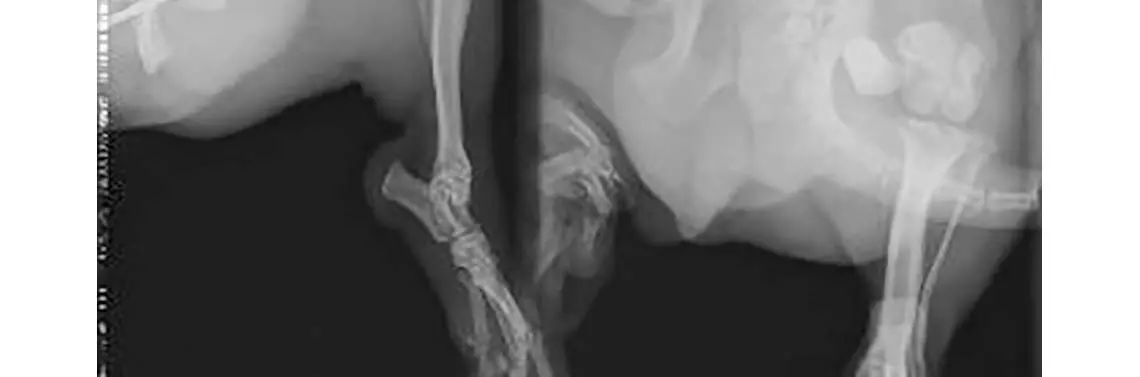

Wykonano zdjęcia RTG w projekcji lewobocznej oraz strzałkowej (fot. 4). Uwidoczniono masywną przebudowę struktur kości udowej z silnym odczynem okostnej odłamu bliższego, cechami osteolizy i znacznego stopnia ścieńczeniem warstwy korowej odłamu dalszego oraz wytworzeniem stawu rzekomego w miejscu przełomu.

RTG boczne i strzałkowe po re-operacji przy użyciu skrzyżowanych gwoździ Kirschnera